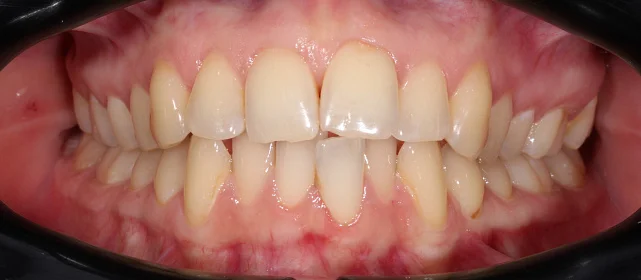

Зубы выровнены, смыкание нормализовано. Установлены несъёмные ретейнеры на обе челюсти, сняты сканы для ретенционных кап. Консультация ортопеда запланирована на более поздний срок.

Решение: Поставили прозрачные элайнеры 3D Smile на обе челюсти. Начали с набора из 34 кап, но в процессе стало понятно, что для полной коррекции нужна доработка — заказали дополнительный набор из 28 кап. Это нормальная ситуация: организм реагирует на перемещение зубов индивидуально, и заранее предсказать точное количество кап до последней штуки невозможно. В итоге 62 капы за 32 месяца — зубы встали на место, смыкание пришло в норму. Параллельно следили за гигиеной, чтобы дёсны оставались здоровыми на протяжении всего лечения.

Основной набор из 34 кап выполнил бо́льшую часть работы, но для финальной коррекции смыкания понадобился дополнительный комплект. Это не редкость — зубы двигаются с разной скоростью, и последние доли миллиметра часто требуют доработки. В итоге получили стабильный результат, который зафиксировали ретейнерами.